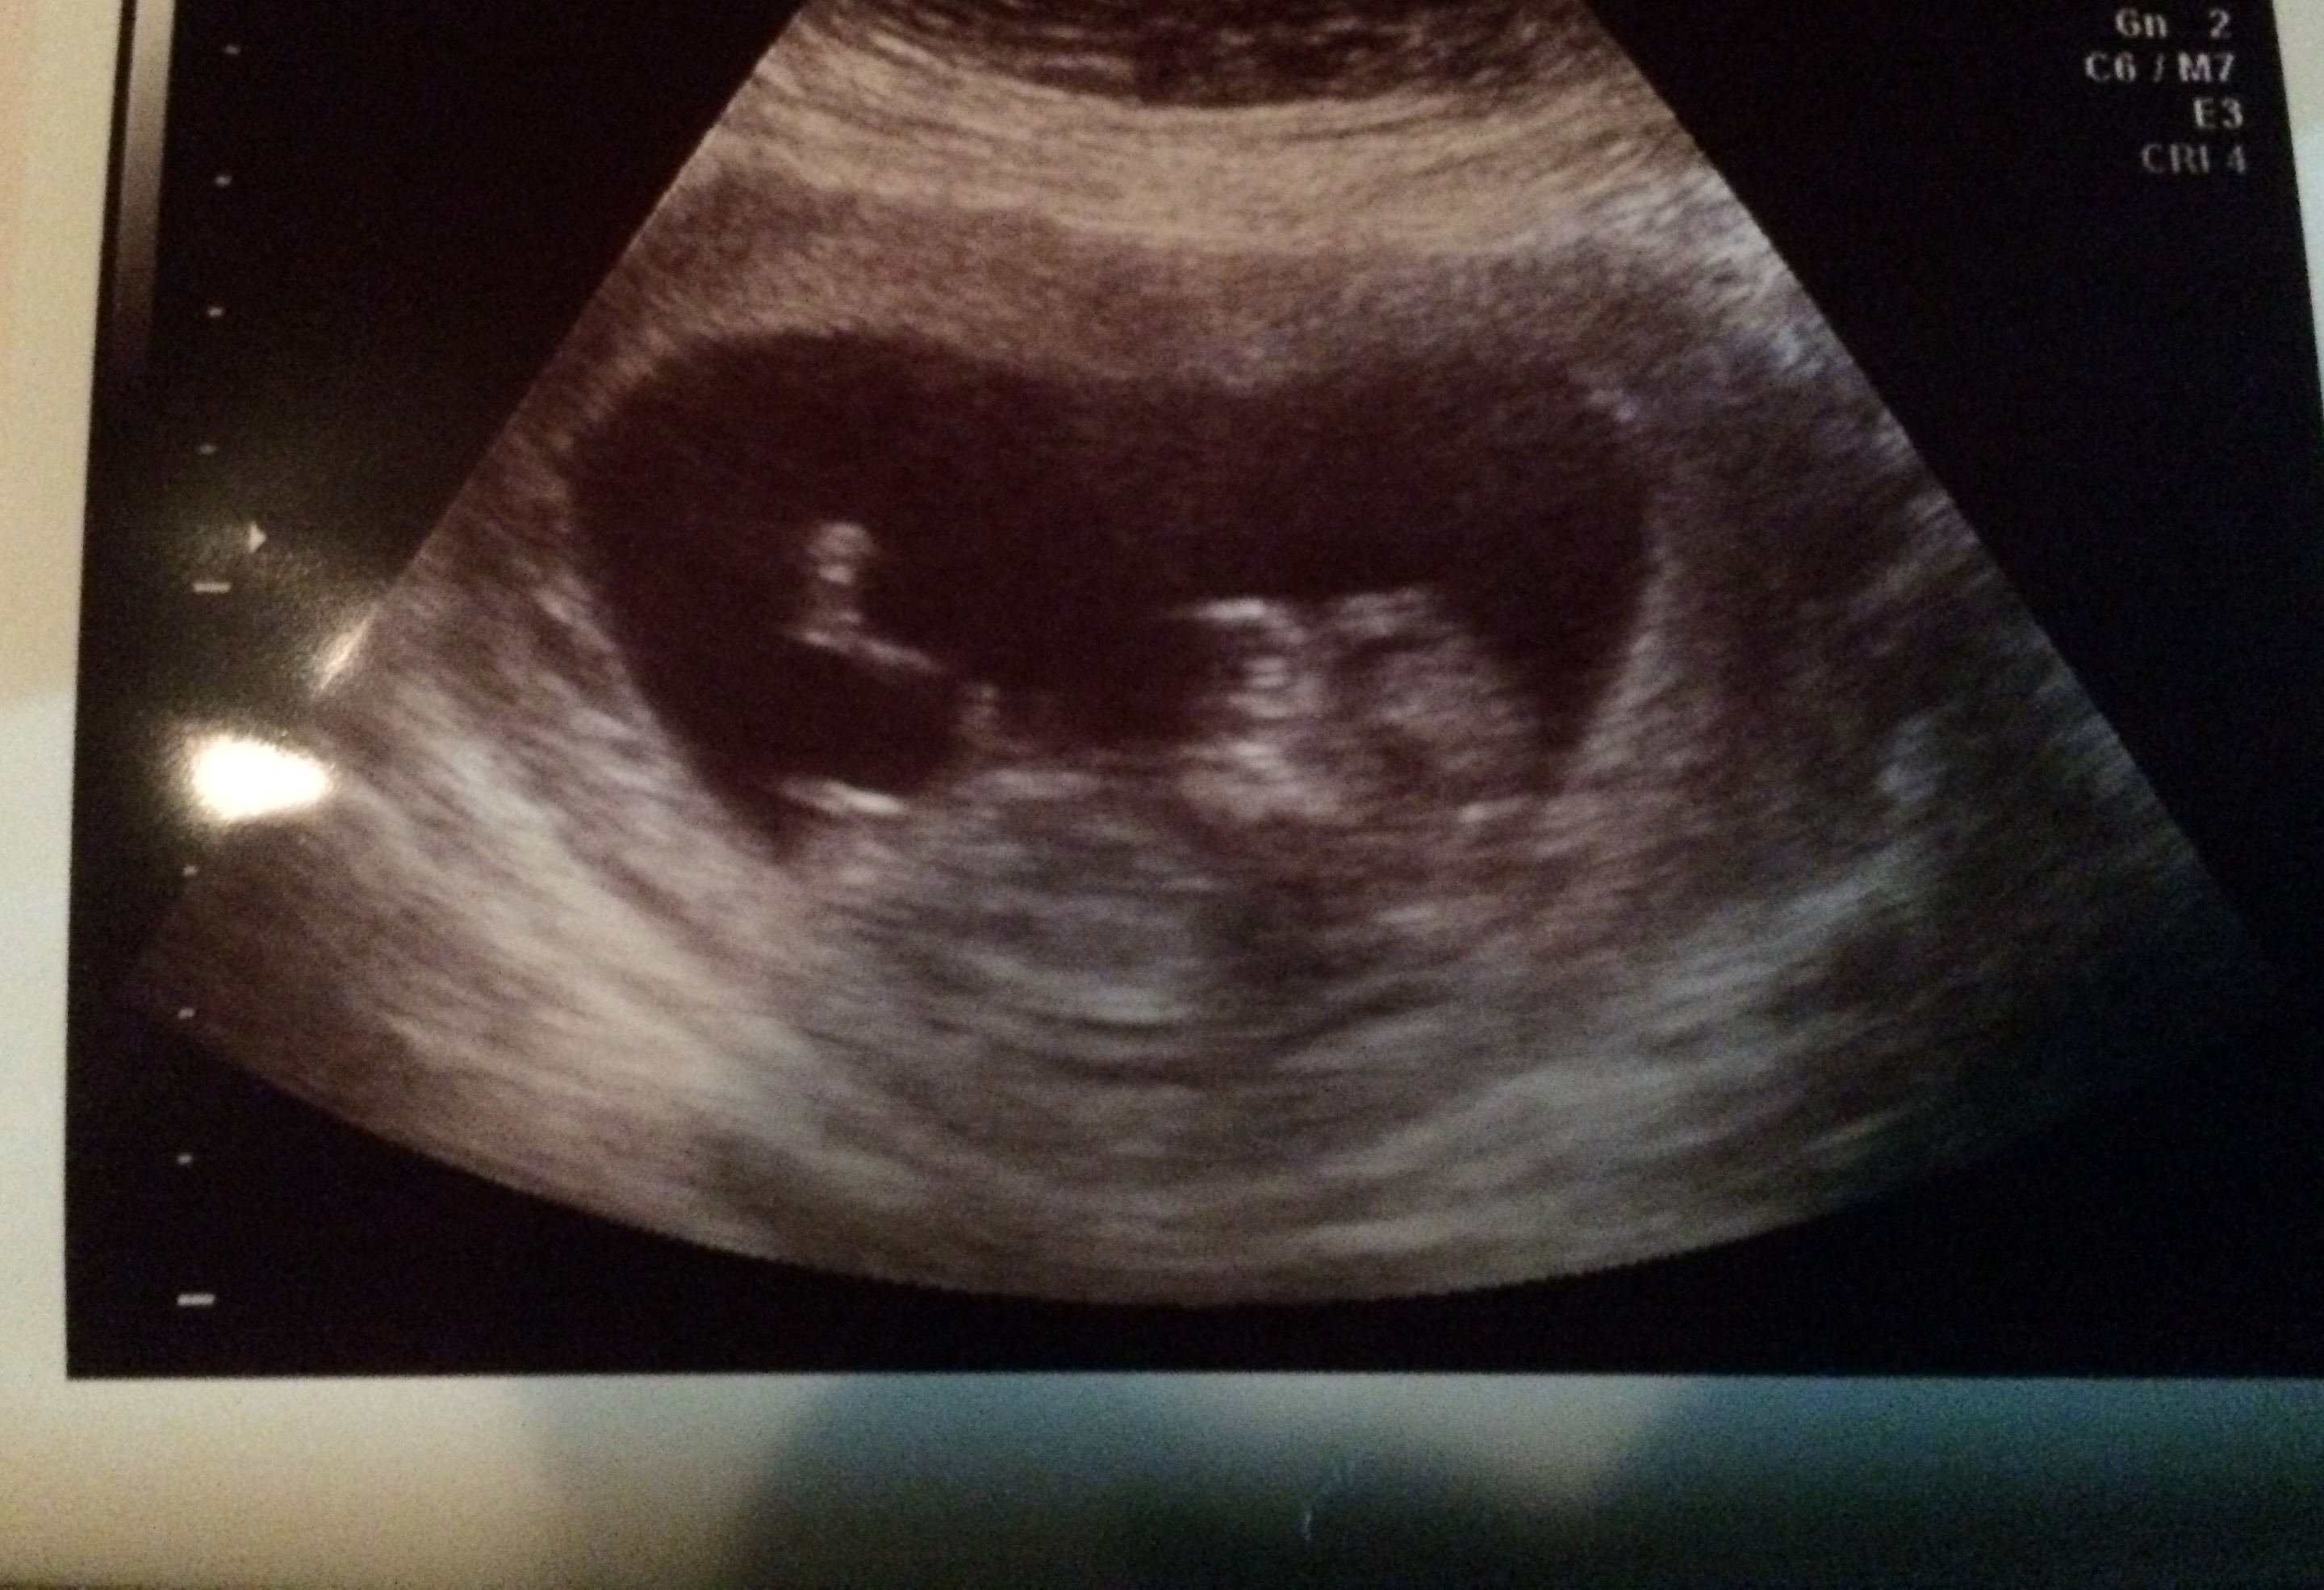

I have two boys and I'm due with my third in July. I was hoping to get some guesses on my 12 week ultrasound. Thank you!!